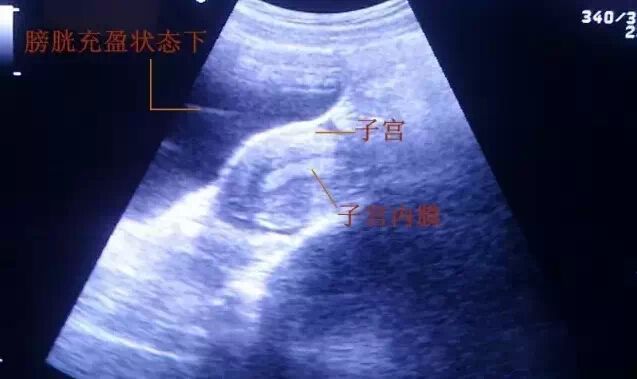

胚胎移植术是采用特制的移植导管将胚胎送入到女性的子宫腔内。所以,在胚胎移植前,手术医生需要在B超引导下观察子宫的位置,而膀胱是子宫的相邻器官,位于子宫前方,憋尿的膀胱在重力的作用下向后压迫子宫,可以让子宫处于比较舒展的状态,使移植导管更容易进入宫腔;另一方面憋尿后,可以通过腹部B超清晰地看到子宫位置及内膜形态,引导医生把胚胎放入宫腔中最合适的地方。

无论是新鲜周期移植还是解冻胚胎移植,在移植前,各位准妈妈们都会被工作人员告知:移植术前要憋尿。当然膀胱内的尿液也不是越多越好。怎样才能保持膀胱内有适量的尿液,避免出现憋尿欠佳或过度的情况呢?